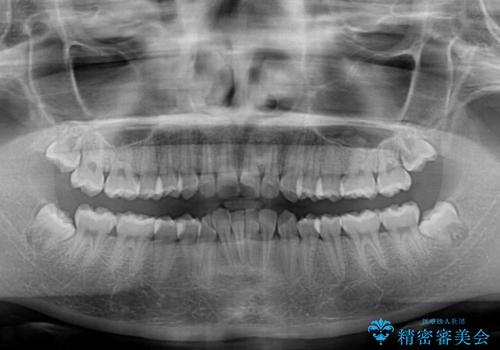

- 上下前歯の叢生を気にして来院された患者様です。

インビザラインでの治療を希望されていて、デコボコの程度が中等度であり、安価なパッケージにて対応可能と判断されたため、インビザライン・モデレートを用いて矯正治療を行うこととしました。